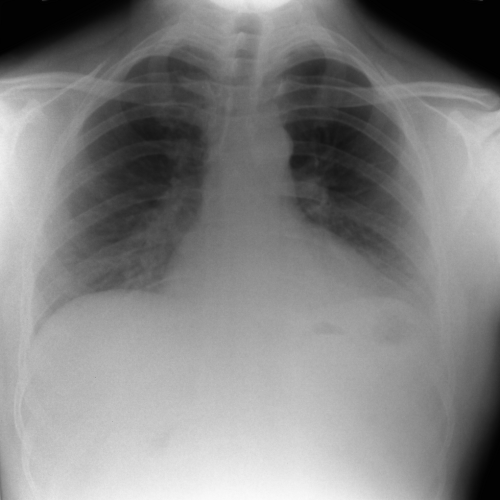

تصاویر بالینی گرفته شده با دستگاه

تصویر قفسه سینه